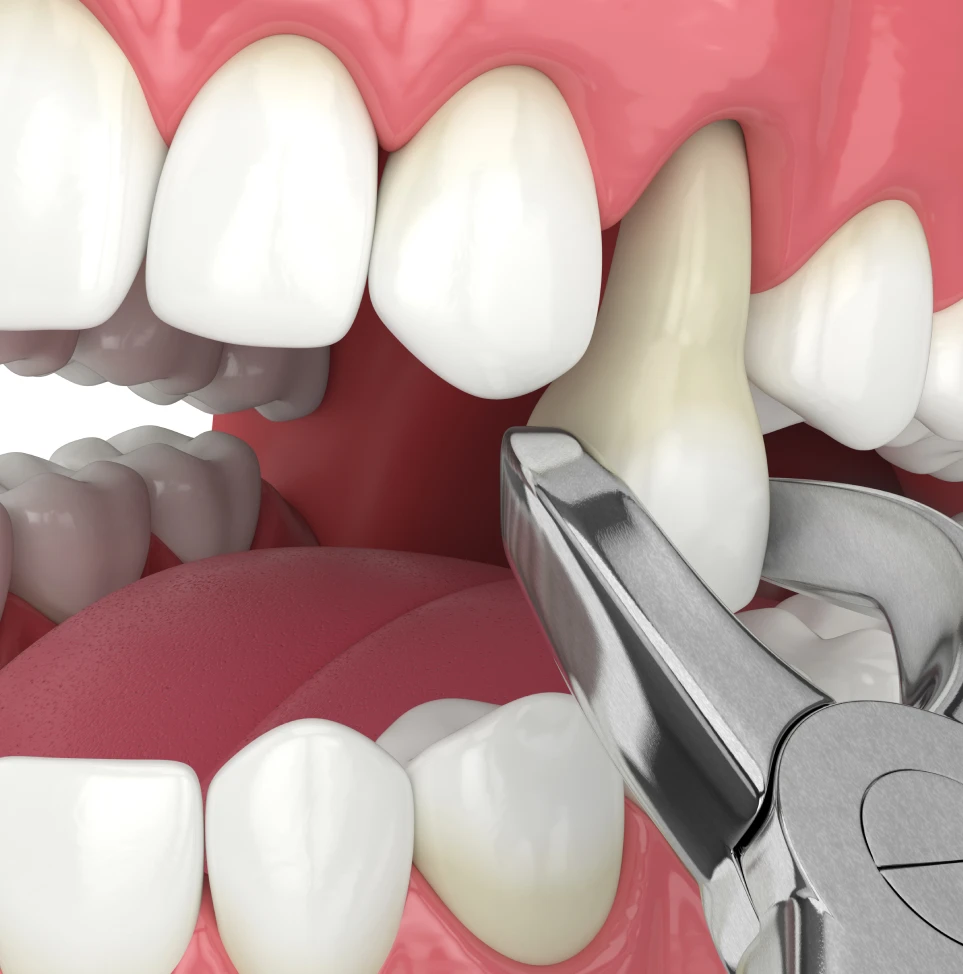

We don’t pull teeth! But we do extract them with the newest and most gentle techniques available.

Unlike tooth extractions of the past, our goal is to preserve the bone around each tooth to maintain the natural anatomy of the mouth and to make the next steps of treatment (i.e., implants or dentures) as predictable as possible.